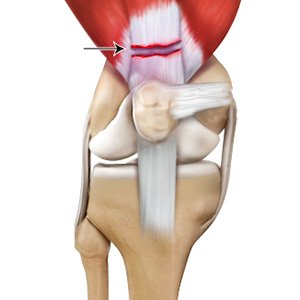

Jumper's Knee

Jumper’s knee, also known as patellar tendinitis, is inflammation of the patellar tendon that connects your kneecap (patella) to your shinbone. This tendon helps in the extension of the lower leg.

Patellar Tendinitis

Patellar tendinitis, also known as "jumper's knee", is an inflammation of the patellar tendon that connects your kneecap (patella) to your shinbone. This tendon helps in extension of the lower leg.